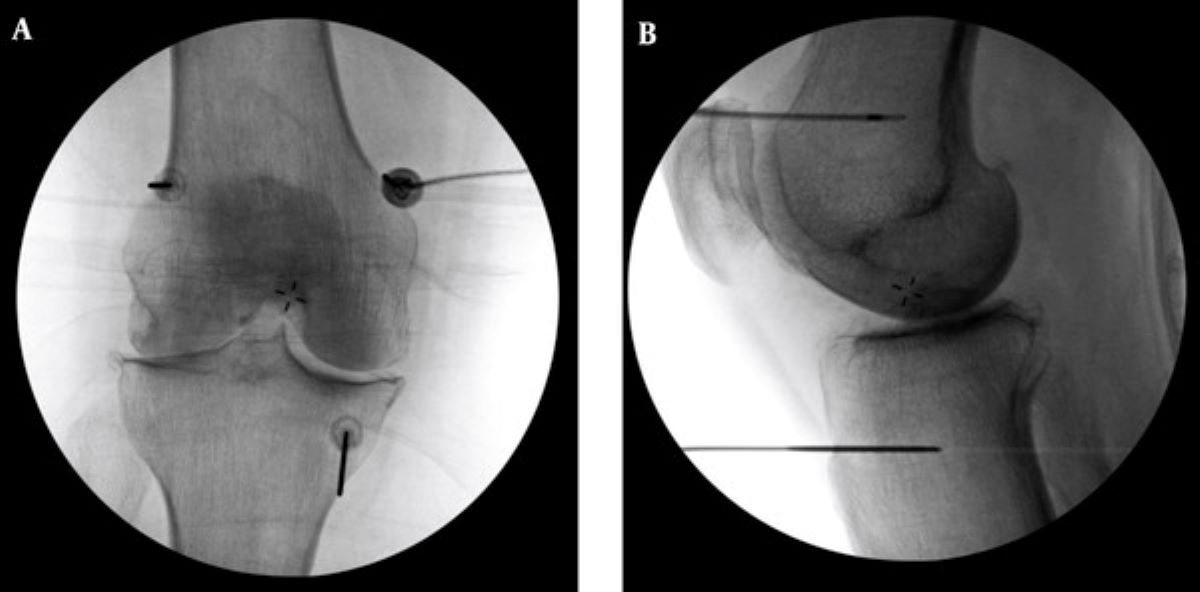

診斷上,退化性關節炎可透過X光查看軟骨縫隙、有無骨刺等,結合身體檢查觀察關節的穩定度、疼痛情況以及是否積水,藉此評估退化程度。原則上,中度以前多能藉由藥物、復健、肌力訓練、生活調整與體重控制改善,中晚期的患者則可能需要置換人工關節,但針對不適合手術或不願手術的患者,則可採用「高頻熱凝療法」止痛。李宜軒醫師說明:「此項技術過往多用於椎間盤突出、滑脫等脊椎神經壓迫造成的下背痛、坐骨神經痛的止痛治療,近來也運用至膝關節退化。執行方式是在局部麻醉的情況下,以X光定位將電極導針導引至膝蓋的三個主要感覺神經叢,確認施行目標後,接上電源線輸出高頻電波,藉由熱能與電效應,使引起疼痛的神經失去傳導疼痛的能力,降低疼痛。」為確保施行過程中未傷及運動神經,治療前會進行不同電量測試,並請病人活動膝蓋,在確定不影響日後活動的情況下進行治療。一般而言,效果會在術後當下至一週內顯現,普遍可維持半年至一到兩年,因人而異。但若有急性感染、心律調節器或正在服用抗凝血劑者即不適用此治療,需由醫師進行評估。